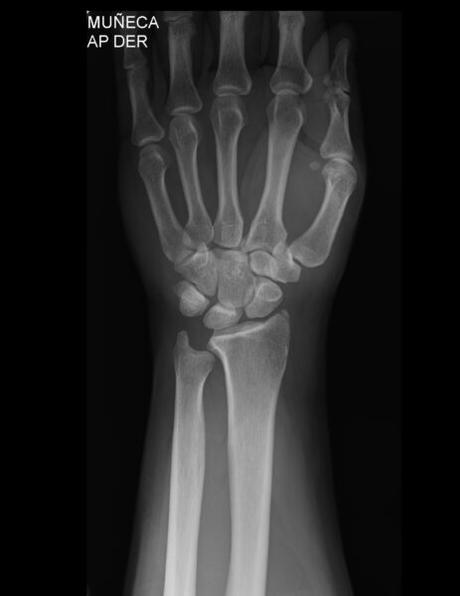

Se obtiene radiografía de mano derecha en proyección dorso palmar, lateral y oblicua, con los siguientes hallazgos:

La densidad mineral ósea es normal en forma generalizada. Las estructuras óseas sin alteraciones en su morfología y alineación. Se demuestran trazos radiolúcidos de fractura transversal incompleta en estiloides radial y oblicua en escafoides no desplazadas. No se demuestran lesiones osteolíticas u osteoblásticas,

FRACTURA DE ESCAFOIDES DERECHO.

FRACTURA TRANSVERSAL DE ESTILOIDES RADIAL.

RESTO DELESTUDIO DENTRO DE LÍMITES NORMALES.